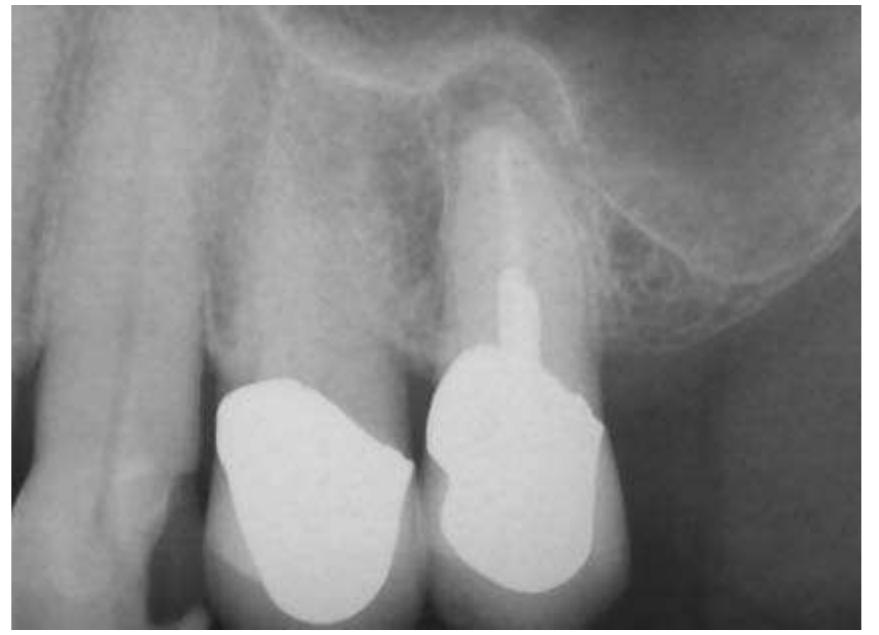

- There is little root filling material present and the root canal would undoubtedly be infected.

- Perhaps the root canal treatment was carried out while the teeth were still vital and the root canals were not infected.

- An attempt at root canal treatment has been made but the root canals are extremely fine and have not been successfully negotiated.

- In the majority of cases, root end surgery would not be carried out unless the root canal had been thoroughly cleaned prior to treatment.